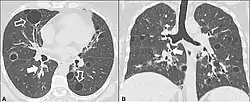

| Left lung completely affected by bullae shown in contrast to a normal lung on the right. | |

In the lungs, emphysema involves enlargement of the distal airspaces,[2] and is a major feature of chronic obstructive pulmonary disease (COPD). Other pneumatoses in the lungs are focal (localized) blebs and bullae, pulmonary cysts and cavities.

Lung cysts

A lung cyst, or pulmonary cyst, encloses a small volume of air, and has a wall thickness of up to 4 mm.[3] A minimum wall thickness of 1 mm has been suggested,[3] but thin-walled pockets may be included in the definition as well.[4] Pulmonary cysts are not associated with either smoking or emphysema.[5]

A lung cavity has a wall thickness of more than 4 mm.[3]